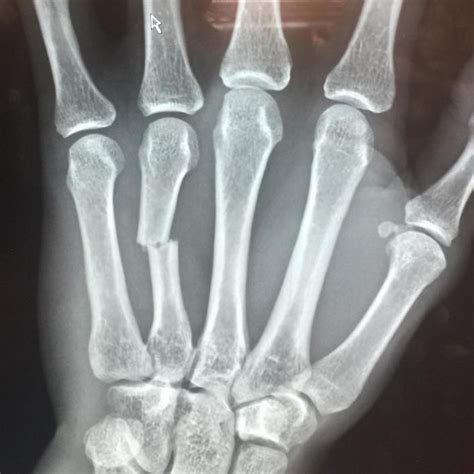

A broken hand x-ray is a type of medical imaging that uses low levels of radiation to produce images of the bones in the hand. These images are crucial for diagnosing fractures, dislocations, and other bone-related injuries. The x-ray machine emits X-rays that pass through the body and are absorbed differently by various tissues. Bones, being denser, absorb more X-rays and appear white on the resulting image, while softer tissues appear darker.

• Fracture Lines: These appear as thin, white lines on the x-ray image and indicate a break in the bone.

• Displacement: This refers to the misalignment of the bone fragments, which can affect the healing process and may require surgical intervention.

• Angulation: This is the angle at which the bone fragments are displaced, which can also impact the treatment plan.

• Soft Tissue Injuries: While x-rays primarily show bones, they can also reveal swelling or other soft tissue injuries that may be associated with the fracture.